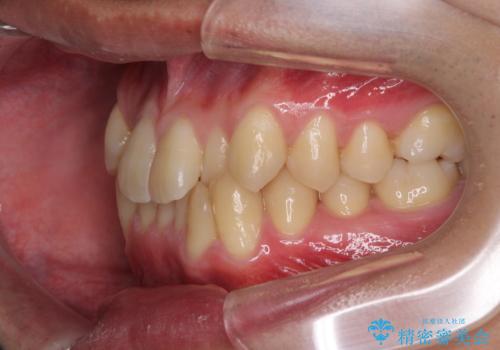

- 前歯のがたつきが気になるとのことで来院されました。

骨格的なところと、上下の歯の大きさのことを考慮して、下の前歯を1本抜歯し、インビザラインにて矯正治療することとなりました。

上の前から2番目の歯がもともと小さかったため、最後にかぶせ物を装着することで、自然な仕上がりにできました。